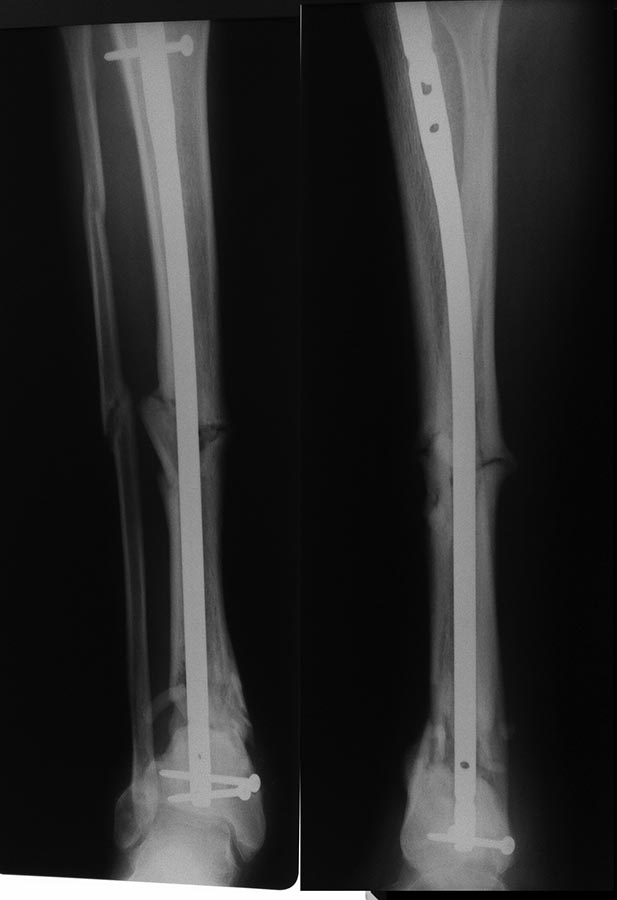

Re: Сегментарный перелом голени в условиях БИОС.

Снимки от мая 2016